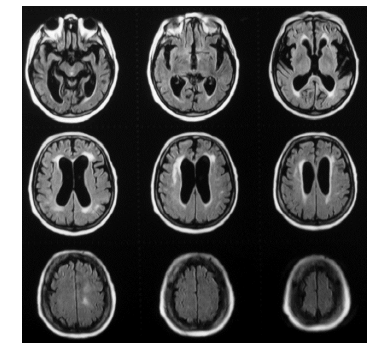

Observe a sequência de imagens abaixo e assinale a alternativa que apresenta sua correta leitura.

Enunciado 2118518-1